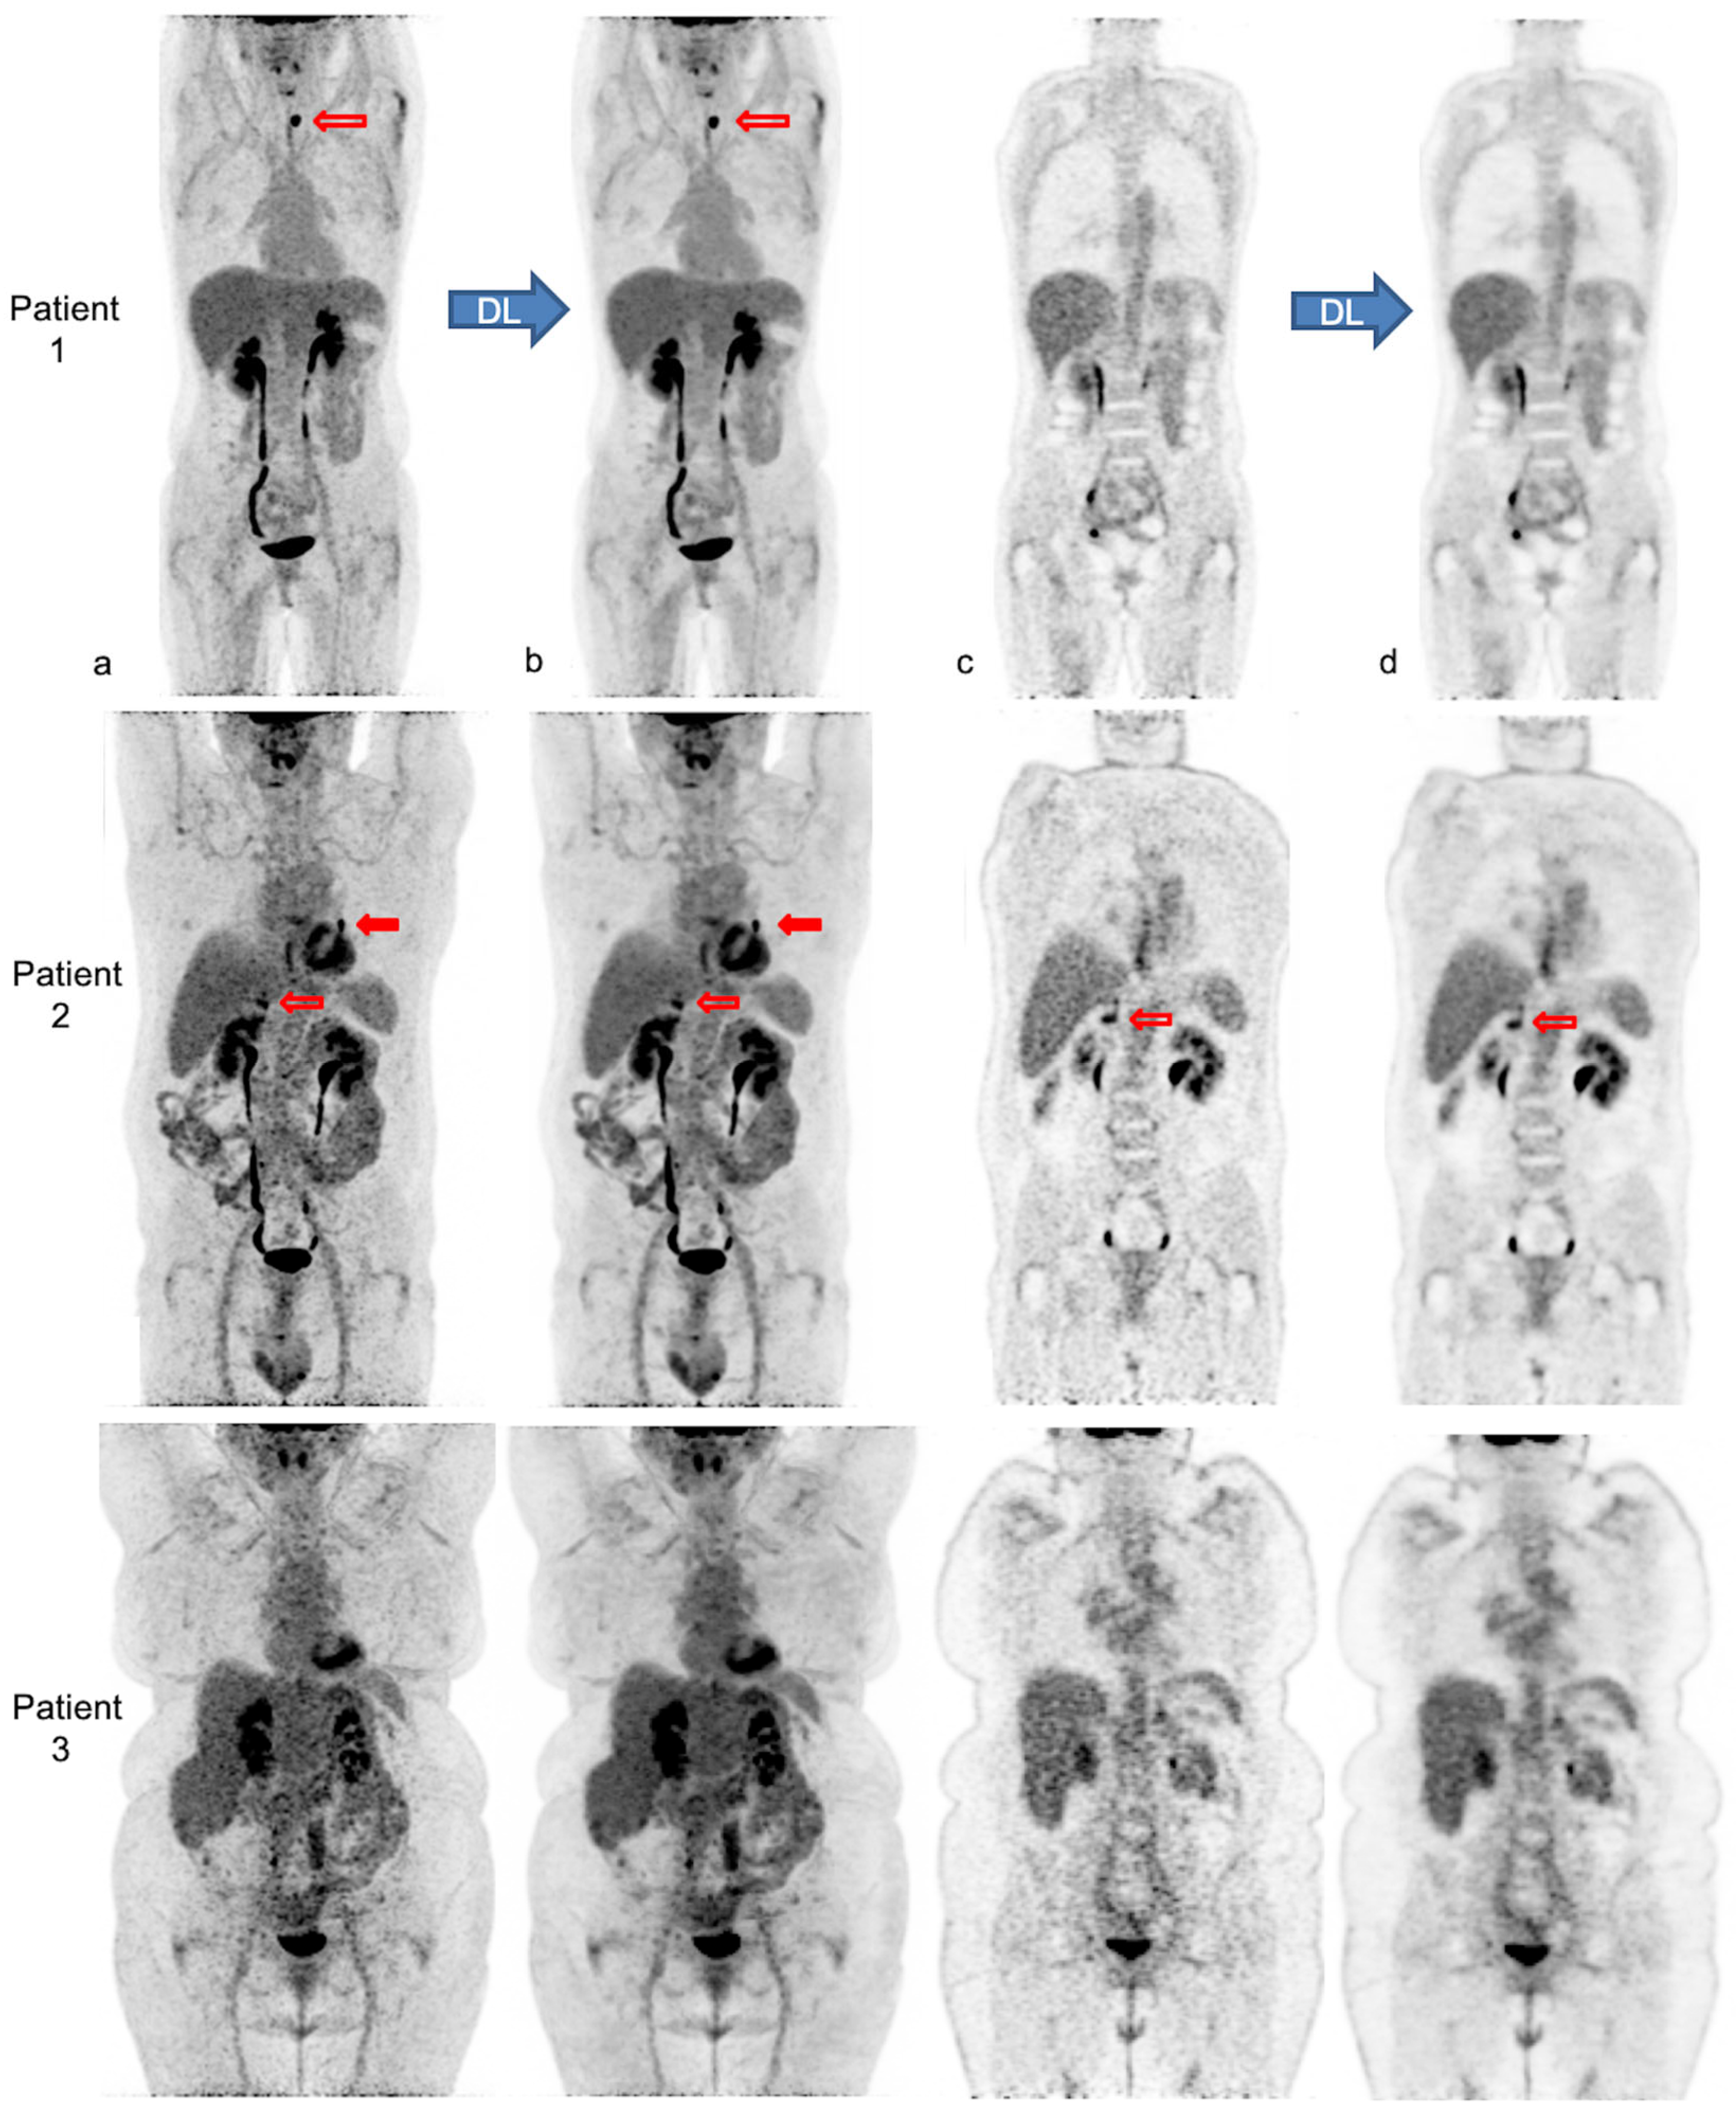

Figure 4 illustrates the impact of body habitus on PET IQ and the improvement and homogenization of IQ after PET denoising in three patients.

Figure 4.

Native and denoised [18F]FDG PET images of three patients with different body habitus. Legend: MIP (a,b) and coronal views (c,d) of native PET (a,c) and denoised PET (b,d), respectively, are illustrated. DL: deep learning processing by Subtle PETTM. Patient 1 is a 36-year-old female with a weight of 55 kg, a BMI 22 kg/m2 and FM of 19 kg, scanned for a suspected paraneoplastic syndrome. The average visual IQ score with native PET was 4 versus 5 with denoised PET and CVliv 9.9% vs. 5.8%, respectively. A [18F]FDG avid left thyroid nodule (red upper arrows), detected similarly in both PET series, proved to be a benign follicular adenoma. Patient 2 is a 63-year-old male with a weight of 89 kg, a BMI of 30 kg/m2 and FM of 27 kg, referred for lung cancer follow-up. IQ score with native PET was 3.5 vs. 4.5 with denoised PET and CVliv 13.4% vs. 7.0%, respectively. The residual left lung lesion (full and upper red arrows) and a right adrenal metastasis (transparent and lower red arrows) were both detectable with native and denoised PET. Patient 3 is a 62-year-old female patient weighing 104 kg with a BMI of 38 kg/m2 and FM of 51 kg. She was scanned for cervical cancer follow-up. IQ score with native PET was 3 vs. 4 with denoised PET and CVliv 15.5% vs. 8.2%, respectively. Both PET showed complete metabolic remission.